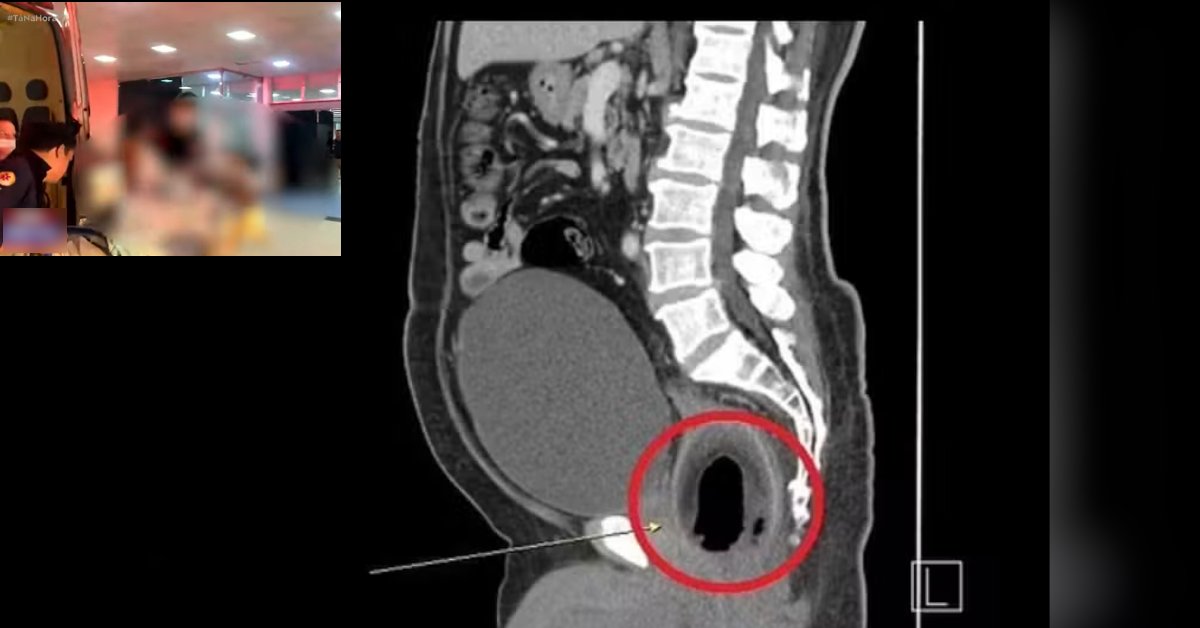

Segundo relatos de um socorrista do Serviço de Atendimento Móvel de Urgência (SAMU), o objeto inserido era de tamanho considerável, assemelhando-se a um coco, o que agravou o quadro clínico do paciente.

Já na capital, o homem foi acolhido pela equipe médica do Hospital de Trauma, referência em atendimentos de alta complexidade. Após avaliação inicial, os profissionais iniciaram uma bateria de exames para compreender a extensão dos danos causados pelo objeto.

Embora o estado de saúde do paciente não tenha sido detalhado, foi informado que a possibilidade de intervenção cirúrgica está sendo considerada, visto que a retirada do objeto pode não ser possível por meios convencionais sem riscos adicionais.